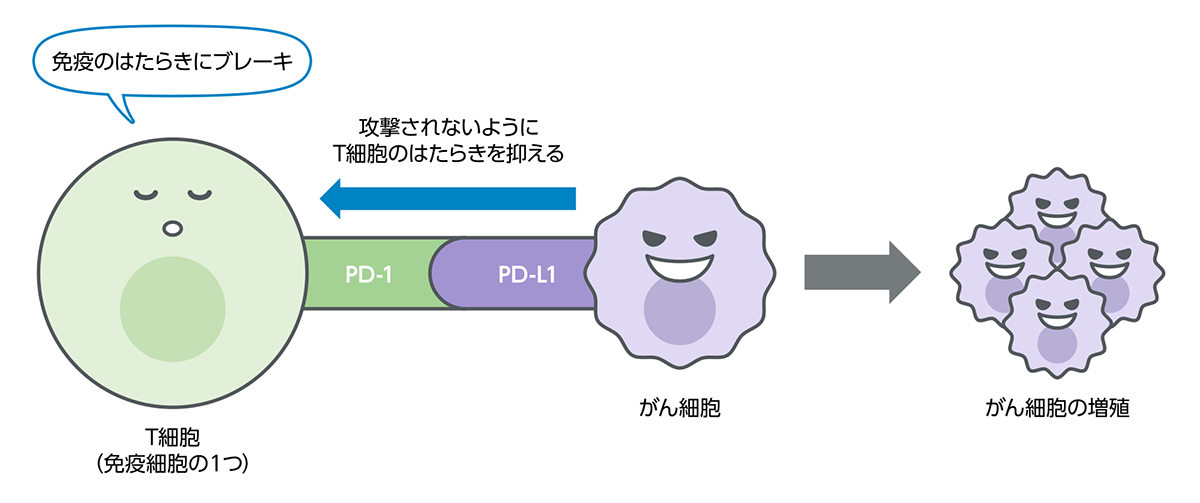

身わたしたちの身体には、体内に入り込んだ異物(自分の体の細胞ではないもの)を攻撃し、排除して体を守る「免疫」という働きが備わっています。

身体の中でがん細胞ができると、免疫の働きがそれを異物ととらえ、排除しようとします。

しかし、がん細胞は、免疫の攻撃から逃れるために、免疫細胞(T細胞など)にブレーキをかける力をもっています。このように、がん細胞によって免疫にブレーキがかけられた状態や、もともと免疫の働きが弱まった状態などでは、がん細胞を排除しきれないことがあります。

免疫の働きにブレーキをかける免疫チェックポイント

私たちの体には、細菌やウイルスなど外来の異物や、体の中でできたがん細胞などの異常な細胞の働きを抑えこみ、排除するための「免疫」という仕組みがあります。さらに免疫が過剰に働き、自分の体を攻撃しないように、免疫にブレーキをかける仕組みも備わっていることがわかってきました。がん細胞の中には、この仕組みを悪用し、免疫による排除から逃れているものもあります。

免疫の働きにブレーキをかける仕組みの1つが「免疫チェックポイント」と呼ばれる分子であり、「PD-1」はその1つです。「PD-L1」はPD-1と結合し、PD-1を活性化させる働きを持つ、細胞表面に存在するタンパク質です。がん細胞の中には、このPD-L1を細胞の表面に出すことによって、免疫の働きから逃れているものがあると考えられています。

免疫のブレーキを解除する治療とPD-L1検査

免疫の働きへのブレーキを解除し、体が本来もつ免疫の力でがんと戦うという治療法が免疫チェックポイント阻害療法です。肺がんでは、PD-1とPD-L1の結合を妨げてブレーキを解除する免疫チェックポイント阻害療法が実用化されています。肺がん細胞の表面にPD-L1がどの程度発現しているかを調べるのがPD-L1検査です。